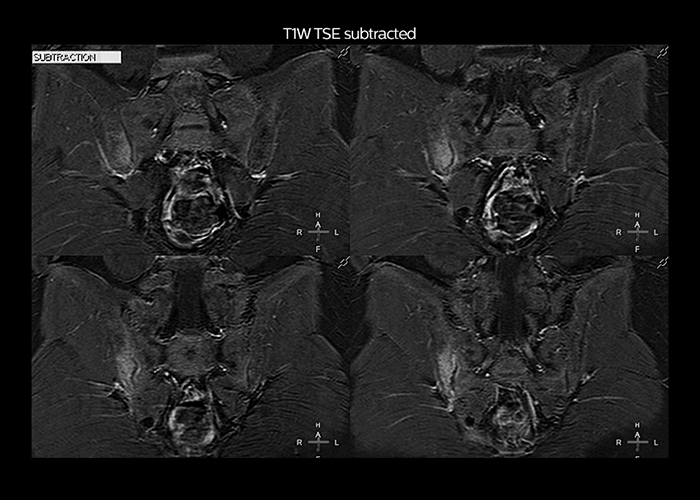

“On average, we scan about 80 patients per day, but on some days we scan well over 100 patients. The scanner is in use 7 days per week, operated 20 hours per day on week days and 8 hours per day in the weekend,” Mr. Tuna says. “To avoid coil changes we plan examinations of similar anatomies back to back, such as head and spine. Multiva helps us here a lot because coils don’t need to be changed frequently. Moreover, thanks to parallel imaging technology and 16-channel HeadSpineTorso and 8-channel MSK coils we are able to achieve excellent image quality. In this way Multiva helped us to increase both image quality and productivity.” “Neurological cases, such as brain and spine imaging, represent the largest share in our MR scanning, followed by musculoskeletal cases. In general, we use simple and basic imaging protocols. But occasionally, we use advanced techniques for problematic cases if necessary.

“Since we have Multiva, we have improved our workflow, because it has been so easy for our operators to learn and use Multiva. Our operators notice that the coils are lightweight and coils don’t need to be changed frequently. The user interface is easy to use. Features like this help us to scan a high number of patients. For instance, the musculoskeletal coils can be used interchangeably, and due to the user-friendly interface, the number of mistakes such as, for example, correct coil element selection has decreased significantly, because the system does it automatically by itself.” “Most important, Multiva satisfies our clinical imaging needs very well,” says Mr. Tuna. “Many features of Multiva have become similar to the Ingenia system. Even in more complex imaging such as abdominal and cardiac, the image quality and performance of Multiva is better than we expected. General surgeons and physicians from our hospital’s internal medicine department prefer to refer to us because of this.”